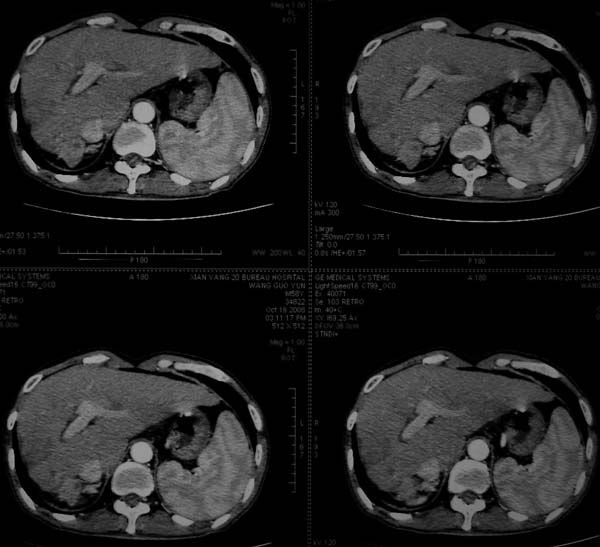

标题: CT16292:男,53岁,上腹部不适2月,B超发现肝内占位病变。 [打印本页]

标题: CT16292:男,53岁,上腹部不适2月,B超发现肝内占位病变。

肝脏体积变小,肝裂增宽,分布异常,肝尾叶增大,脾肿大,考虑肝硬化可能性大,右肝病灶呈现早期充盈,延迟强化考虑肝内胆管细胞癌可能,不除外血管瘤

肝硬化,多结节肝癌。比较典型的表现了。

肝叶比例失调,左叶增大,肝裂增宽,脾脏增大,门脉增宽,肝右叶包膜下多发结节样阴影,增强虽说强化幅度不大,但还是符合快进快出特点;考虑肝硬化、脾大、结节型肝癌。胆管细胞癌多有延时强化、肝包膜凹陷征、周围胆管扩张等特点,本例明显不符;故不考虑。